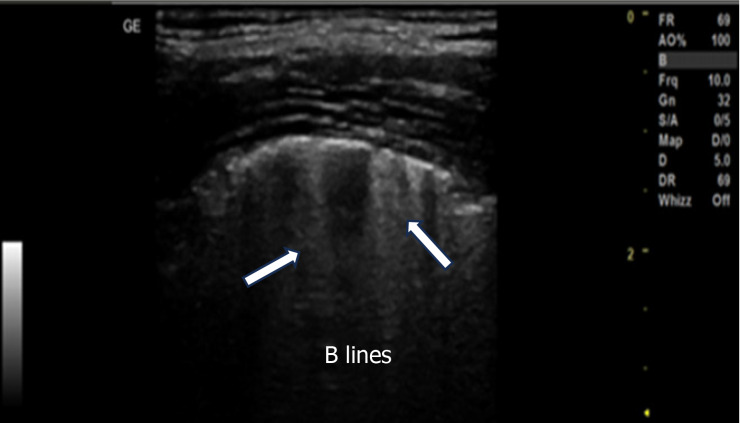

Background: Lung ultrasonography is being increasingly used in mechanically ventilated patients to evaluate the lung aeration during incremental positive end expiratory pressure (PEEP) adjustments and to evaluate the weaning process from mechanical ventilation. The effects of PEEP may vary across different lung pathologies and may not consistently correlate with changes in lung aeration as assessed by lung ultrasound scores (LUSs).

Aim: To assess the role of lung ultrasonography in evaluating lung aeration during the application of PEEP in mechanically ventilated patients with various lung pathologies.

Conclusion: Increasing PEEP levels in mechanically ventilated patients improves lung aeration, which can be effectively assessed using bedside lung ultrasonography.